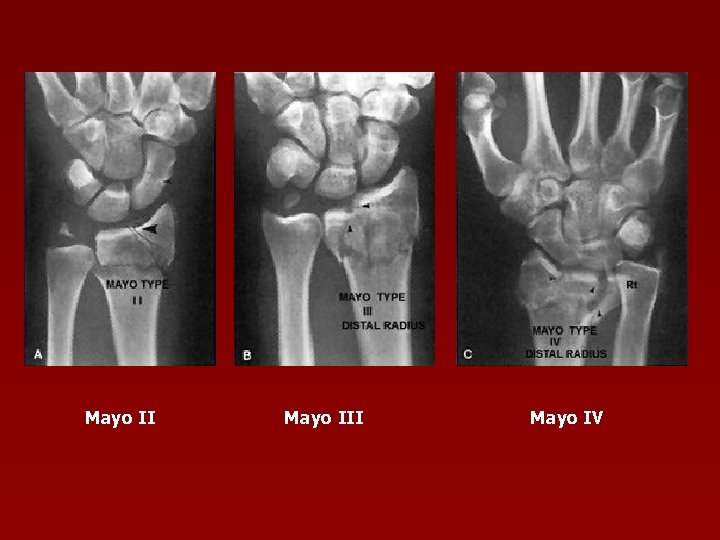

Clasificarea Mayo a fracturilor intraarticulare distale radius Tip I – intraarticulare, fără deplasare (extraarticulare faţă de articulaţia radiocarpiană) Tip II – implică articulaţia radioscafoidiană, cu deplasare Tip III – implică articulaţia radiolunată, cu deplasare Tip IV – implică articulaţia radioscafoidiană şi radiolunată, cu deplasare

Mayo II Mayo IV